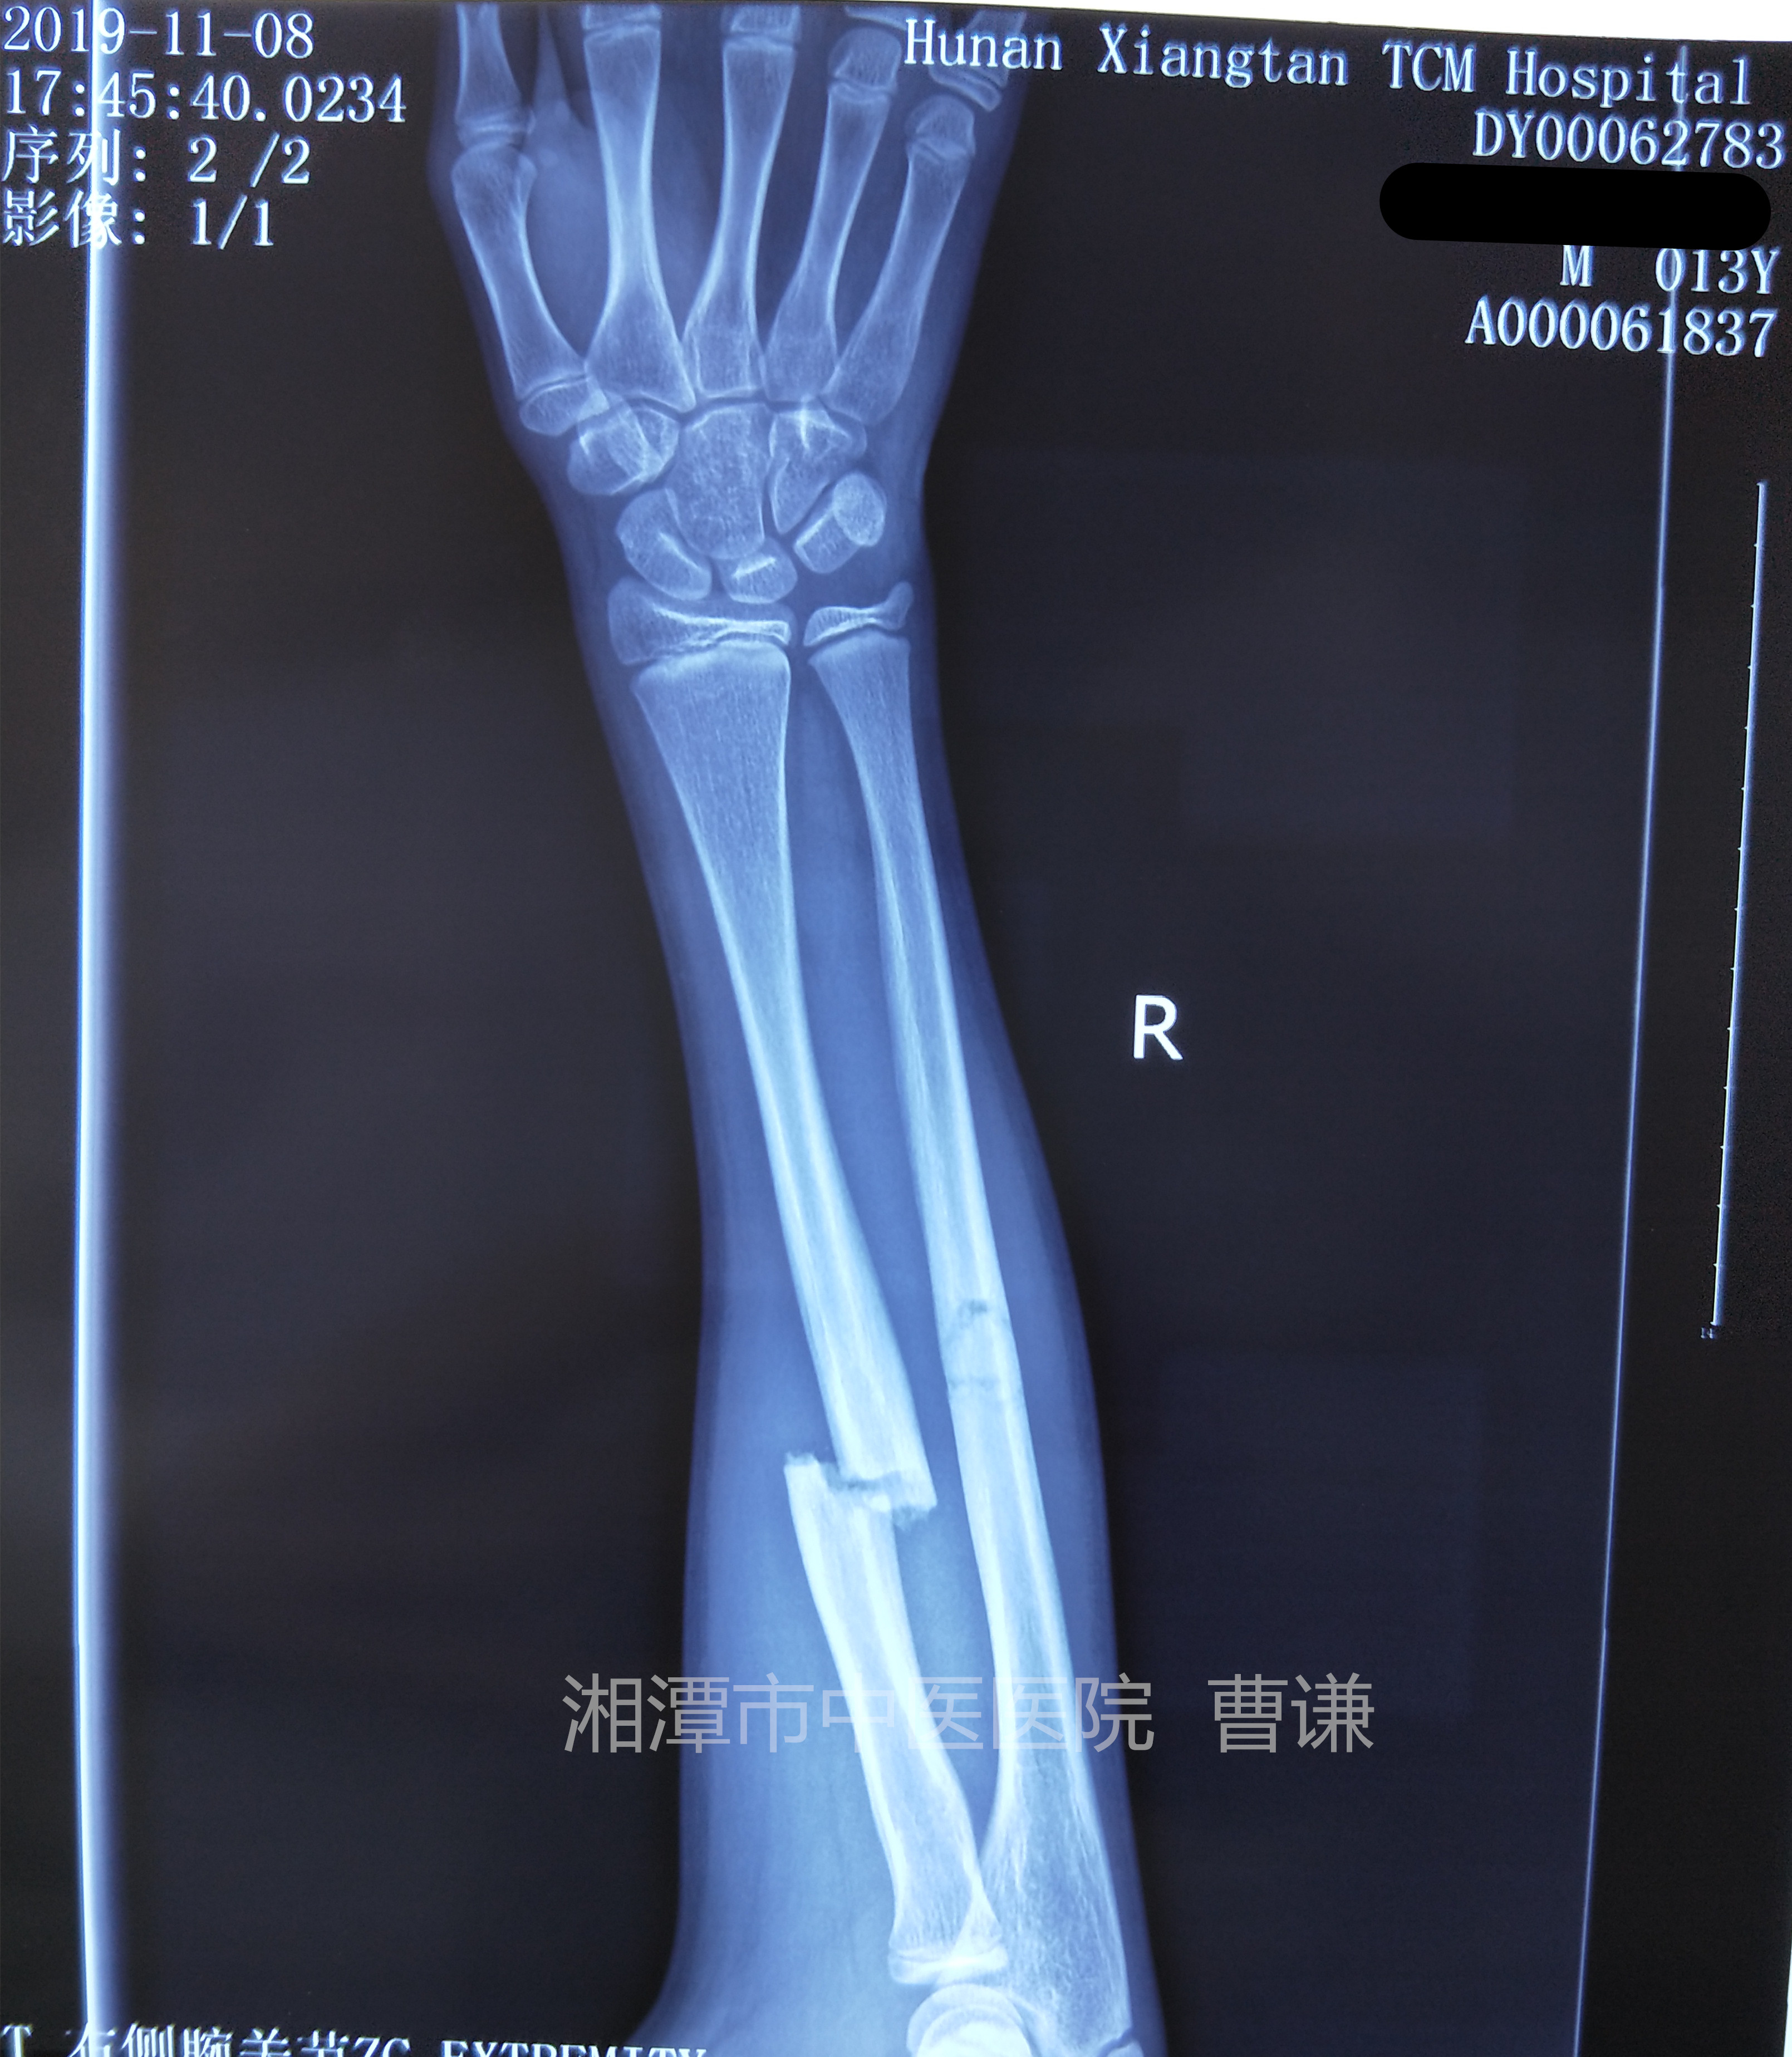

入院拍片情况如下: